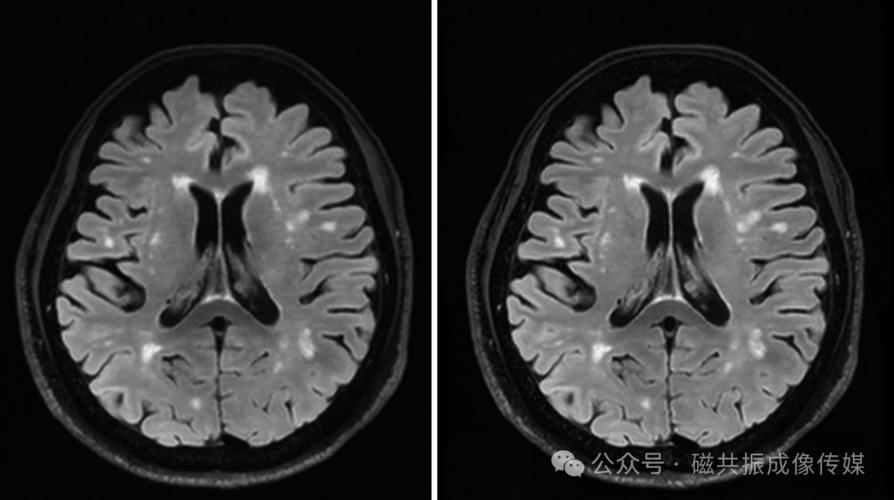

- 医学成像:在MRI(磁共振成像)中,分块CS可以显著缩短扫描时间,提高患者舒适度,并减少运动伪影。